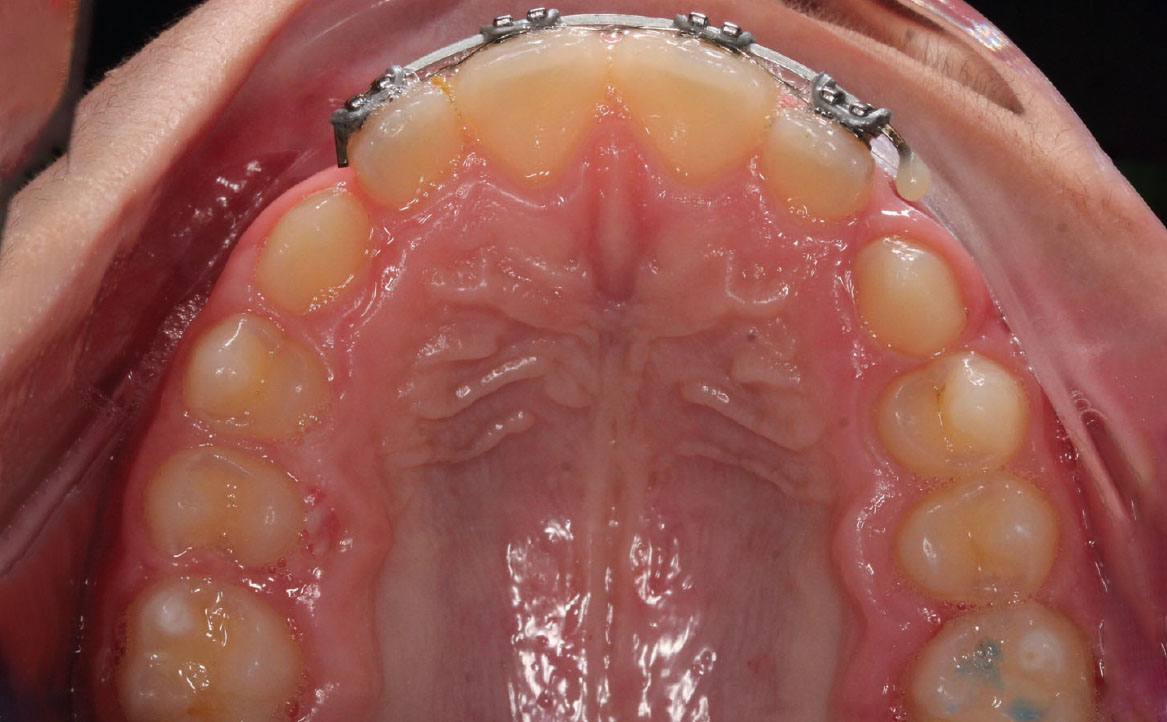

L’overjet e l’overbite sono entrambi ridotti in massima intercuspidazione. Trasversalmente il mascellare superiore è contratto (fig. 4-7).

Fig. 6A Foto dell'arcata superiore.

Fig. 6B Modello digitale dell'arcata superiore.